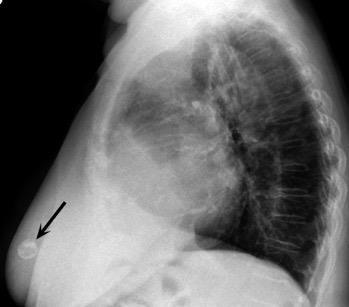

Nódulo en língula.

Cirugía de Ca .de mama hace 23 añosedema de brazo y ganglio en axila. ¡Metástasis!.

Ecanow JS et l. Axillary Staging of Breast Cancer: What the Radiologist Should Know. Radiographics 2013